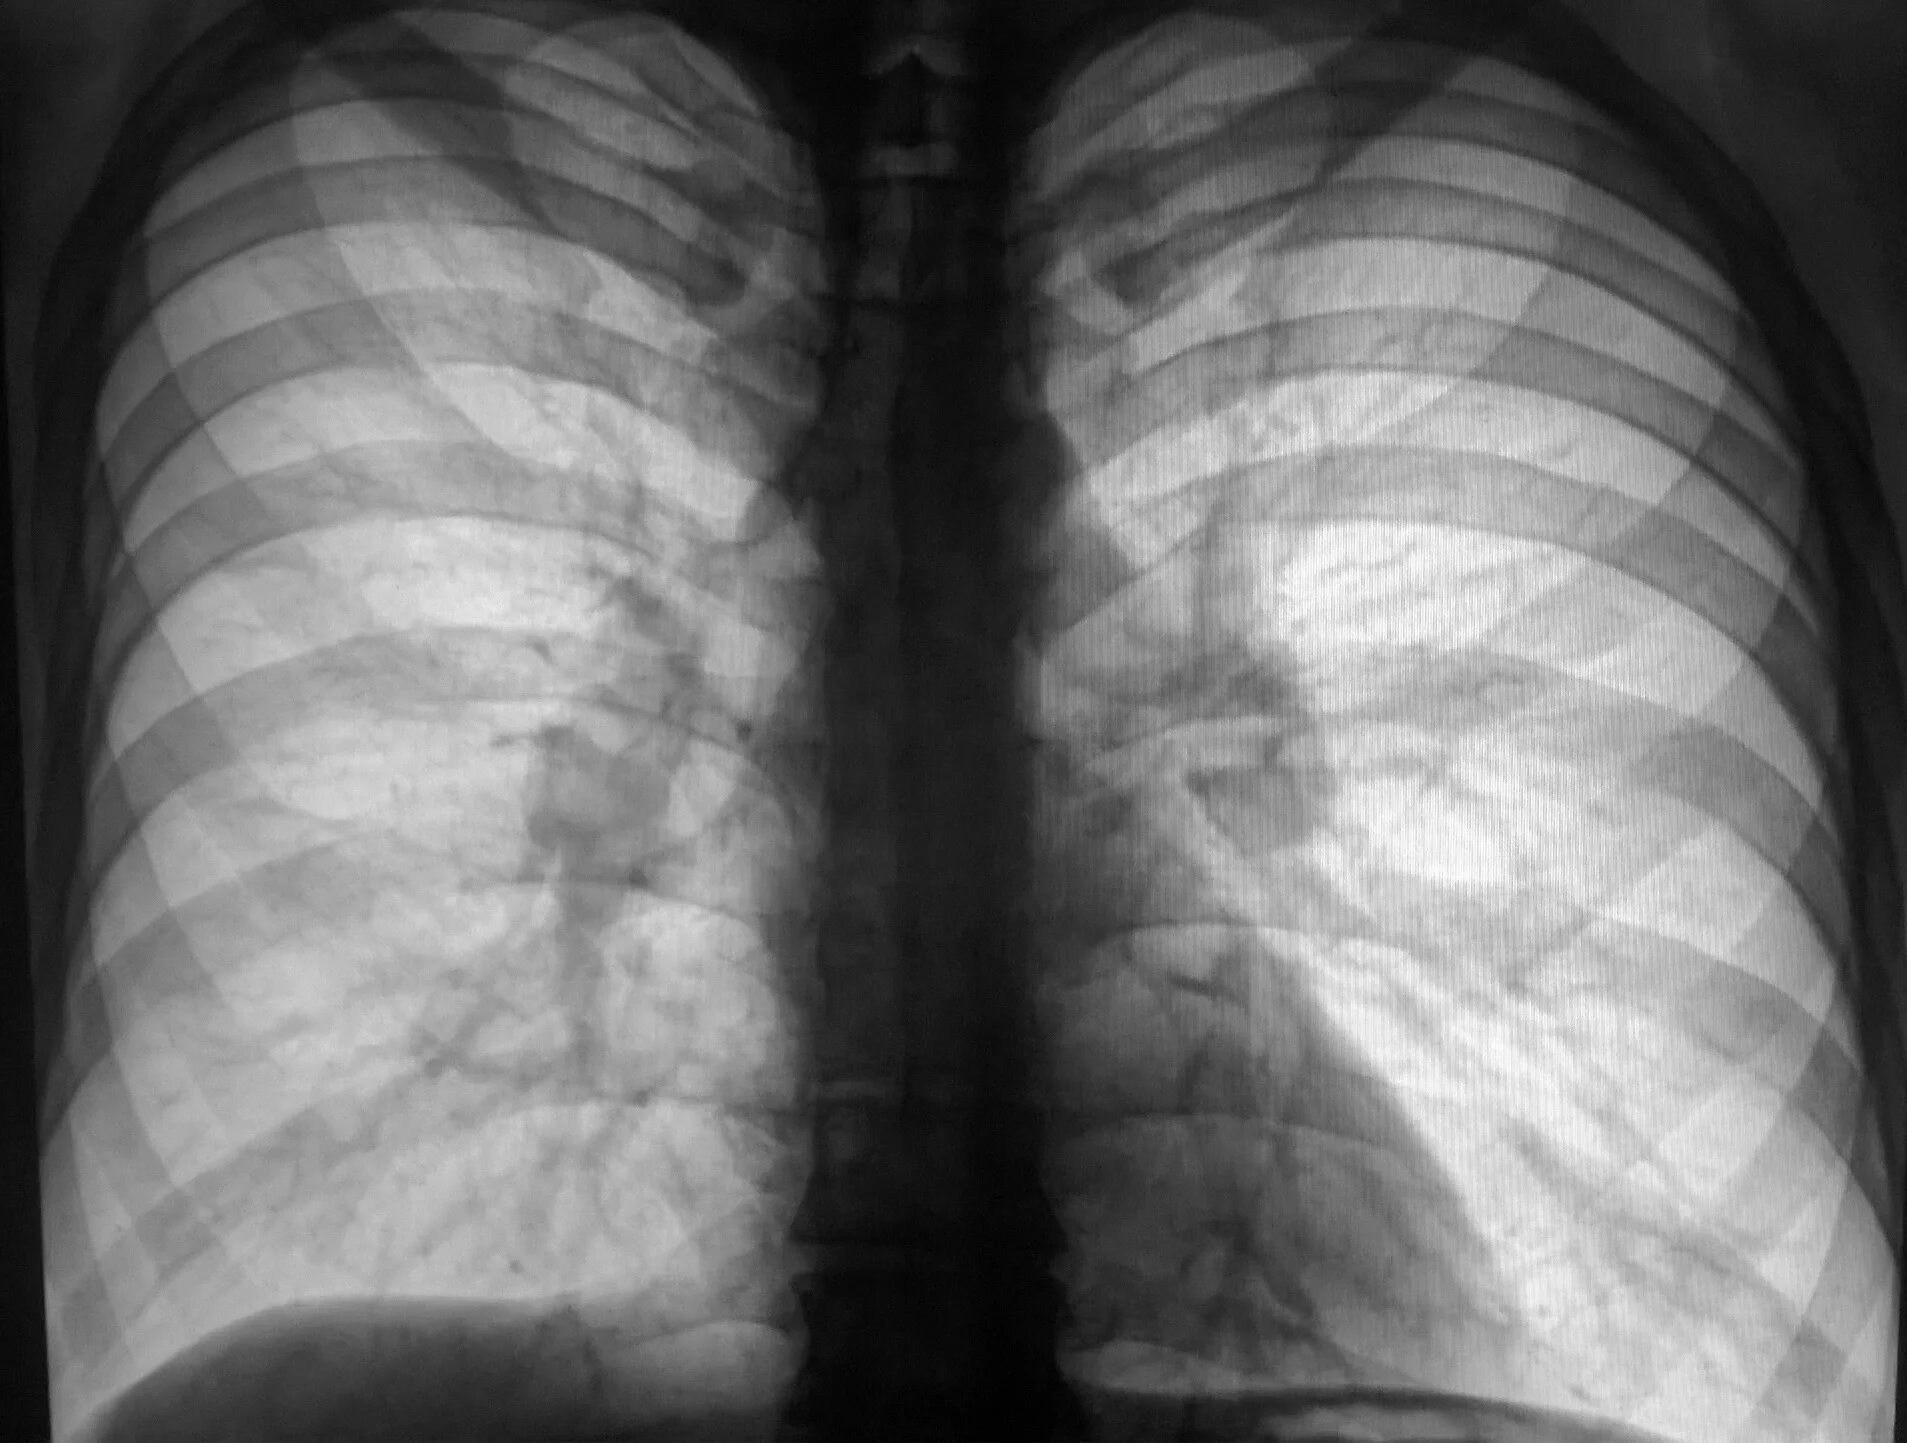

Диффузный эндобронхит